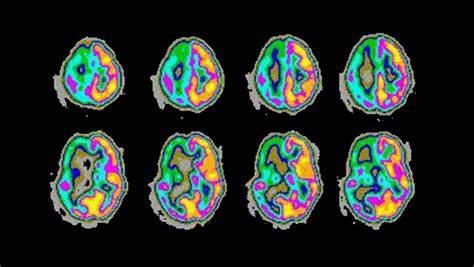

癫痫发作时孩子的大脑会发生什么?这里有个简化的解释:您的大脑由数十亿个称为神经元的神经细胞组成,它们通过微小的电脉冲相互交流。当大量电池同时发出电荷时,就会发生癫痫发作。这种异常而强烈的电波会淹没大脑并导致癫痫发作,从而导致肌肉痉挛、意识丧失、行为异常或其他症状。

小儿癫痫发作怎么办?患儿一旦出现癫痫,就应当到医院就诊,行头颅CT、MRI扫描以排除颅内病变;同时要行脑电图检查,较好是视频脑电检查,好帮助医生明确病因诊断。